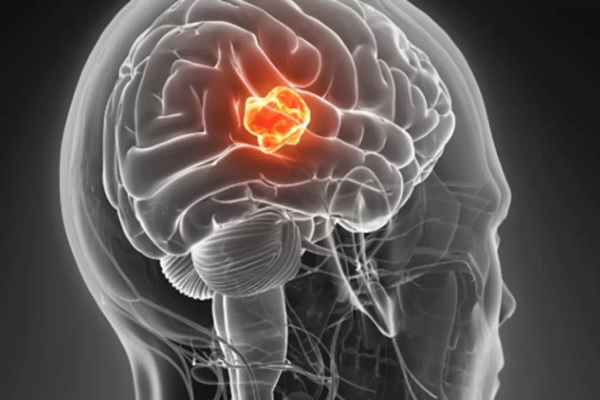

۵ راهکار ساده برای کنترل و درمان تومورهای مغزی لاعلاج

دانشمندان میگویند برخی استراتژیها در زندگی میتواند به کنترل و درمان تومورهای مغزی کمک کند.

به گزارش اقتصادآنلاین نقل از باشگاه خبرنگاران ، لتل تومورهای مغزی یکی از مرگبارترین بیماریهایی محسوب میشوند که از هر صد هزار نفر در بین مردان ۳.۶ نفر و از هر صدهزار نفر در بین زنان ۲.۵ نفر دگیر این بیماری میشوند. از ۹ میلیون و ۵۰۰ هزار مرگ و میر سالانه سرطان در جهان، ۲۴۱ هزار مورد (۲.۷۱ درصد) متعلق به تومور مغزی است.

به گزارش ثینگز، با این حال، با برخی استراتژیها میتوانید از بروز تومور مغزی جلوگیری کرده و حتی این بیماری را به طور طبیعی التیام دهید. از مهمترین این استراتژیها میتوان به موارد ذیل اشاره کرد: